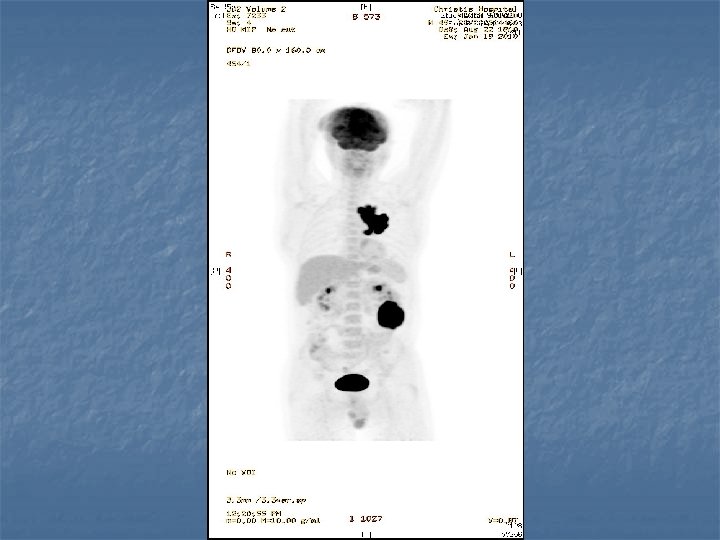

n n n PRETREATMENT INVESTIGATIONS: FBC, Renal and liver function, LDH, urate, Ig. GS. Histology review. Marrow aspirate+trephine (cytogenetics, immunology) CD 4 , HIV viral load. CT Scans. (MR Brain) (PET scan ) Echo / LVEF CMV, Hep B+C, Toxoplasma serology MAI screen. LP for CSF cytology +/- intrathecal Rx. (DLBC , Burkitt, Plasmablastic).